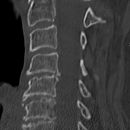

Deckplatte LWK 2 ohne Hinterkante